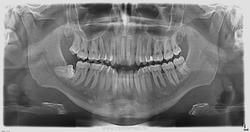

Поперечный перелом тела нижней челюсти слева через лунку пятерки, перелом коронки этой же пятерки. Коварный... Практически без смещения... И второй перелом справа, на угле, через лунку полуретинированной и аномально заложенной 8...

Анатолий Владимирович, почему, на Ваш взгляд, нет ни разрыва кортикала...ни малейшего смещения отломков?...на обзорных краниограммах четких данных за переломы тоже нет...я в сомнениях....

Это ему повезло, потому что переломы без смещений, по типу трещин. Я с стоматологией работал, бывают такие, поэтому и назвал их коварными... когда будут удалять пятерочку - корень элеватором - все проявится. Ну и естественно через дней 10-12 в динамике...

Коллеги....не было бы сомнений, я бы снимок не выкладывал...но- прошло БОЛЕЕ 10 суток от момента травмы...почему так неубедительно, так слабо, выглядят "как бы линии переломов"...вот в чем вопрос? Уж не игра ли теней? Не хочется никому ничего лишнего "привесить"....

По поводу зуба все ясно...там то точно - перелом.

А вот с 8 - я бы подождал... Ну раз смещения нет - дай Бог обойдется без остеомиелита. Время покажет!

Дополнительно к написанному: кажется имеется косой перелом подбородка идущий справа налево до межзубного промежутка 2-3